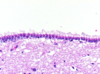

What are these cells?

What do they line?

Ependymal cells

Line ventricles